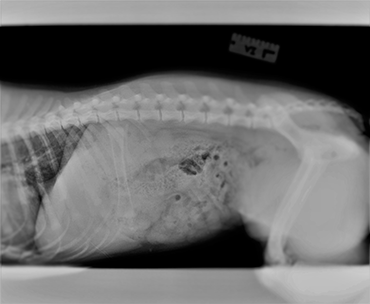

Puppy swallowed chicken bone online, Mischievous pup nearly died after swallowing a chicken bone PDSA online

My puppy ate hotsell a chicken bone online, My Dog Ate a Chicken Bone Now What MetLife Pet Insurance online, Mischievous pup nearly died after swallowing a chicken bone PDSA online, Don t Panic When a Dog Eats a Cooked Chicken Bone online, My Dog Ate a Chicken Bone What to Do Canna Pet online, What to do if my shop dog swallowed a chicken bone online, Dog swallowed chicken store bone without chewing online, Does My Dog Need to Go to the Vet After Eating Chicken Bones PetHelpful online, Dog swallowed 2024 chicken wing online, Dog swallowed a store chicken bone whole online, Dog ate a shard of a cooked chicken bone. The emergency vet did an X ray photo below and said that it s so small that they re not concerned about it and to not online, Are raw chicken bones good for dogs Bold By Nature online, Dog ate chicken bones what to jointed do online, Dog ate a shop whole chicken bone online, I hate that i think about money first but id give and arm n a leg vet emergency chickenbone dog dogsoftiktok goodboy scared veterinarian online, My puppy shop swallowed a bone online, Help My Dog Ate a Chicken Bone Here s What To Do BETTY BUTCH online, my dog ate chicken bones and i need advice r DogAdvice online, What to do if your cheap dog swallows a chicken bone online, What Should I Do if My Dog Ate Chicken Bones PetHelpful online, My dog swallowed shop a whole bone online, What to Do if Your Dog Ate Chicken Bones online, My dog swallowed store a chicken bone whole online, What To Do If Your Dog Eats A Chicken Bone AKC Pet Insurance online, What To Do If Your Dog Eats A Chicken Bone online, My Dog Ate Chicken Bones Should I Be Worried Heart Paw online, My Dog Ate a Chicken Bone Now What MetLife Pet Insurance online, What do I do if my dog ate a chicken bone Everett Vets online, What to Do if Your Dog Ate Chicken Bones online, What to Do if Your Dog Eats a Chicken Bone Arrowhead Animal Hospital online, Cooked Bones Are Dangerous For Dogs Our Blog Animal Emergency Service online, Dog Ate Chicken Bones Don t Panic Here s What To Do Kingsdale Animal Hospital online, My Dog Ate Chicken Bones Whole Dog Journal online, Dog swallowed chicken store leg bone whole online, My Dog Ate a Chicken Bone What Do I Do Vet Answer Dogster online, Product Info: Puppy swallowed chicken bone online.